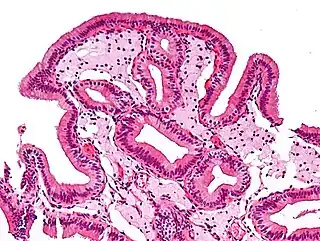

![]() Células espumosas en colesterolosis de la vesícula biliar. | ||

Las células espumosas aparecen en la pared de vasos sanguíneos formando una veta de grasa. Este es el inicio de la formación de la placa de ateromas y son derivadas de macrófagos y células musculares lisas de la pared arterial. En casos de hiperlipidemia crónica, las lipoproteínas conglomeradas dentro de la íntima de los vasos sanguíneos se oxidan por la acción de los radicales libres generados ya sea por los macrófagos, células endoteliales o, especialmente en placas avanzadas, también de células musculares lisas.[1] Los macrófagos digieren las lipoproteínas de baja densidad (LDL) oxidadas por un proceso llamado endocitosis, dirigidos por receptores scavenger, que son distintos de los receptores de LDL. La LDL oxidada se acumula en los macrófagos y otros fagocitos, que luego son conocidas como células espumosas.[2] Estas forman estrías de grasa en las placas de ateroma de la túnica íntima de las arterias.

Las células espumosas no son peligrosos en sí, pero pueden convertirse en un problema cuando se acumulan en ciertos focos específicos, creando así un centro necrótico en el proceso de ateroesclerosis. Se puede formar una capa fibrosa a raíz del centro necrótico que puede luego despegarse de la luz de un vaso, formando un trombo que puede conducir a embolias que ocluyen vasos más pequeños. La oclusión de pequeños vasos da como resultados la isquemia, que contribuye al accidente cerebrovascular e infarto de miocardio, dos de las principales causas de muerte cardiovascular relacionadas con la aterosclerosis.